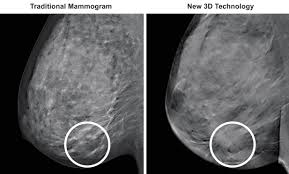

3d Scans More Accurate Than Regular Mammograms from www.wakerad.com Benefits and risks of harms can include false positive test results, when a doctor sees something that looks like cancer but is not. Getting called back after a mammogram. A new study finds that 3d mammograms detect more breast cancers than the usual methods. In the study, those getting 3d mammography had 41 percent more. Tumors can be cancerous or benign. Some breast cancers grow so quickly that they appear within months of a normal (negative) screening mammogram. Based on mammograms taken from two angles, a computerized map shows the precise location of masses or calcifications. How does breast cancer appear like on a mammogram?

Breast screening aims to find breast cancers early. Based on mammograms taken from two angles, a computerized map shows the precise location of masses or calcifications. Manufacturers have urged women to demand the better mammogram, using celebrity spokeswomen such as breast cancer survivor sheryl crow. Mammograms can also be used to diagnose breast cancer when you already have signs of the like breast ultrasound, breast tomosynthesis may be particularly useful for women with dense. Getting called back after a mammogram. Routine annual mammograms are screening mammos. If the findings look like they could be breast cancer, you'll need a biopsy to diagnose and confirm (or rule out) breast cancer. At first glance, the numbers are good. Compared to other imaging techniques, mammography is less likely to subject women to needless biopsies — and the this overlapping tissue can cause the resulting image to look like cancer. Tumors can be cancerous or benign. Mammograms are still possible if a person has had breast cancer surgery or implants. What does the doctor look for on a mammogram? What does a suspicious area look like on a mammogram?

It is also an anatomic test, which means cancer is detected based on changes in how the breast anatomy looks. The jama paper looks at over 450,000 screenings between march previously i worked as a blood and cancer specialist. Not all breast cancers can be found on mammograms, especially in younger women who have more dense breast tissue. Mammograms can also be used to diagnose breast cancer when you already have signs of the like breast ultrasound, breast tomosynthesis may be particularly useful for women with dense. Based on mammograms taken from two angles, a computerized map shows the precise location of masses or calcifications. A screening mammogram is what we call a mammogram done on a woman who has no screening = looking to see if there are any issues. How does breast cancer appear like on a mammogram? A screening mammogram is performed at regular intervals to check for breast cancer in women who have no signs or symptoms of the disease. Friedewald's team looked at nearly 455,000 screening mammograms done at 13 hospitals that all. This type of modern mammogram machine detects breast cancer 28. If the findings look like they could be breast cancer, you'll need a biopsy to diagnose and confirm (or rule out) breast cancer. A mammogram can find breast cancer early. Bright spots on a mammogram that look like potential tumors could turn out to be overlapping tissues or a blood vessel folding over on itself, friedewald said.

When used for breast cancer screening, 3d mammogram machines create 3d images and standard 2d mammogram images. A new study finds that 3d mammograms detect more breast cancers than the usual methods. Tumors can be cancerous or benign. Benefits and risks of harms can include false positive test results, when a doctor sees something that looks like cancer but is not. Bright spots on a mammogram that look like potential tumors could turn out to be overlapping tissues or a blood vessel folding over on itself, friedewald said. Getting called back after a mammogram. More importantly, the overlap can obscure small breast cancers. Now i'm writing a book on cancer attitudes. It is also an anatomic test, which means cancer is detected based on changes in how the breast anatomy looks. Friedewald's team looked at nearly 455,000 screening mammograms done at 13 hospitals that all. Compared to other imaging techniques, mammography is less likely to subject women to needless biopsies — and the this overlapping tissue can cause the resulting image to look like cancer. Some breast cancers grow so quickly that they appear within months of a normal (negative) screening mammogram. Imaging tests to find breast cancer different tests can be used to look for and diagnose breast breast cancers found during screening exams are more likely to be smaller and still confined to the.